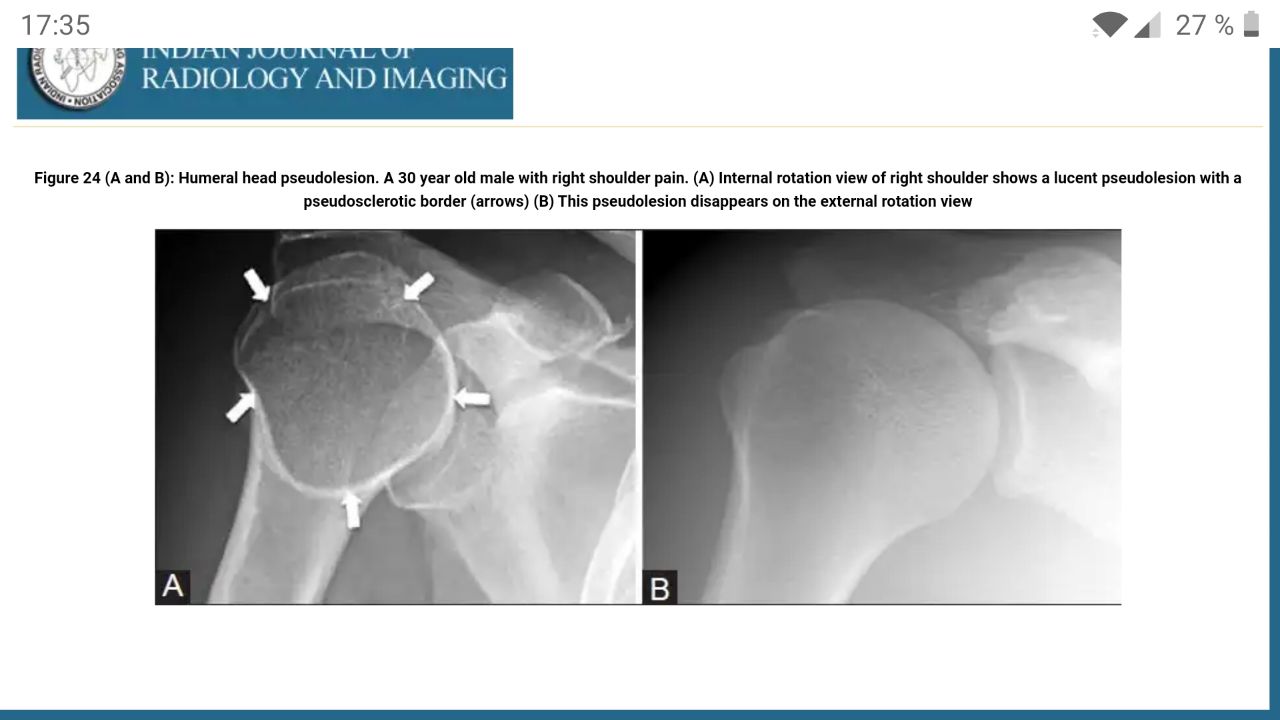

Это вроде норма. Просто переснять с наружной ротацией.

Добрый день. Пациентка, 37 лет. Жалобы на боли в правом плечевом суставе. В 2018 году имело место обращение к онкологам, предположительно направительный диагноз остеома. Пациента нет, опросить и доснять возможности нет. Размер зоны интереса 4*4,5 см.

Вау, очень показательно